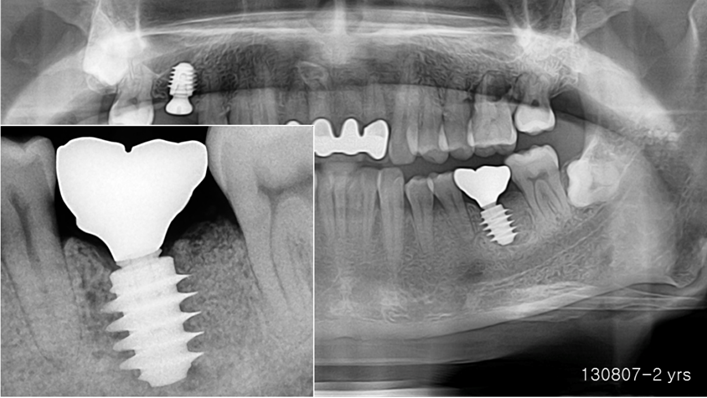

Clinical case: Bone filling into the bottom of deepest thread at 8.0mm AnyRidge fixture

- Courtesy of Dr. Kwang Bum Park -

Keywords

AnyRidge, Knifethread ,extraction socket, ,initial stability ,Allograft, ,osseointegratio ,Dr. Kwang Bum Park, , Mandibular, Single replacement, AnyRidge, Mega-oss,

Products used

Implant system-AnyRidge, Regeneration-Mega-Oss

“AnyRidge implant enables fast and stable

osseointegration at this extreme case of bone defect. ”